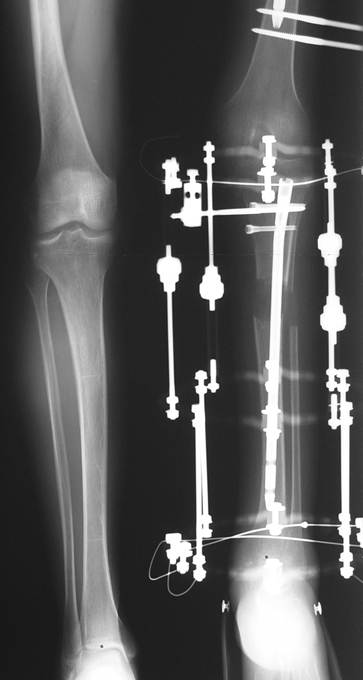

2. DEVELOPMENTAL LOWER LIMB SHORTNESS

This includs lower limb shortness which occurs following growth plate disruption and growth arrest, Ollier’s Disease, multiple osteochondomatosis, poliomyelitis, infection, radiation (radiotherapy), cerebral palsy, spina bifida, club foot and similar disorders. Additional abnormalities are frequent in this group. Many cases can be treated with one or two lengthening operations. If present, deformity can be corrected simultaneously with shortness. For condirtions that damage the hip joint at the first year of life like neonatal sepsis, we reconstruct the hip joint with pelvic support osteotomy in addition to lengthening, and a hip joint with nearly normal function is acquired.